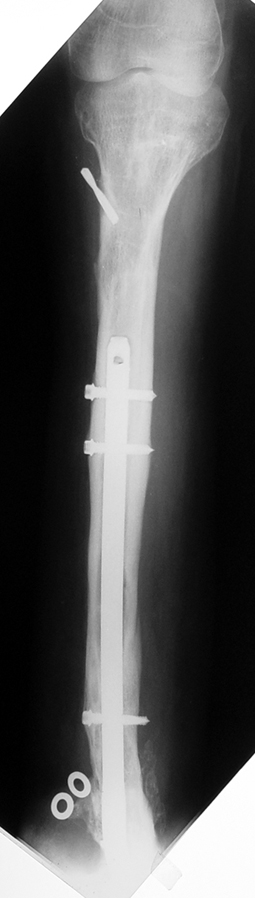

Bu Bacak Kısalık tipi bir kırığın kısalmış pozisyonda kaynaması ile oluşur. Bir çok vaka yetişkinlerde görülür ve sadece bir uzatma ile tedavi edilebilir. Ek deformiteler de aynı anda düzeltilebilir. Bu hastaların çoğu çivi üzerinden uzatma veya tam implante edilen çivi ile tedavi edilebilirler.